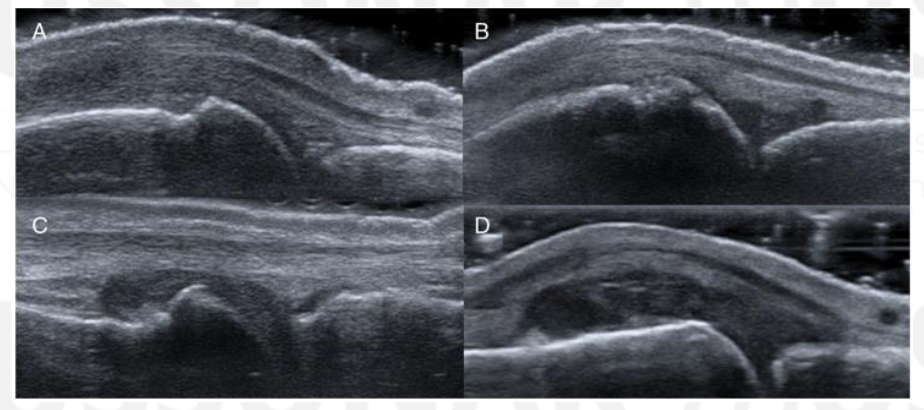

What view is this?

PIP

Synovium

Extensor Tendon

Proximal Phalanx

Middle Phalanx